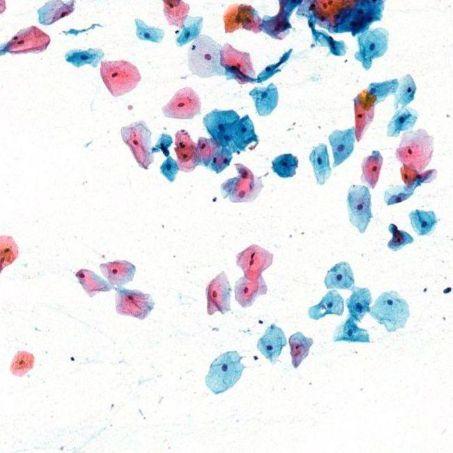

Programming Capabilities Designed for Preferences

Option 1: Select a Default Staining Program

Staining default programs, progressive and regressive

Option 2:  Customize your own with easy programming capabilities

Orange / Blue Color Variability

Intensity (How Light or Dark)